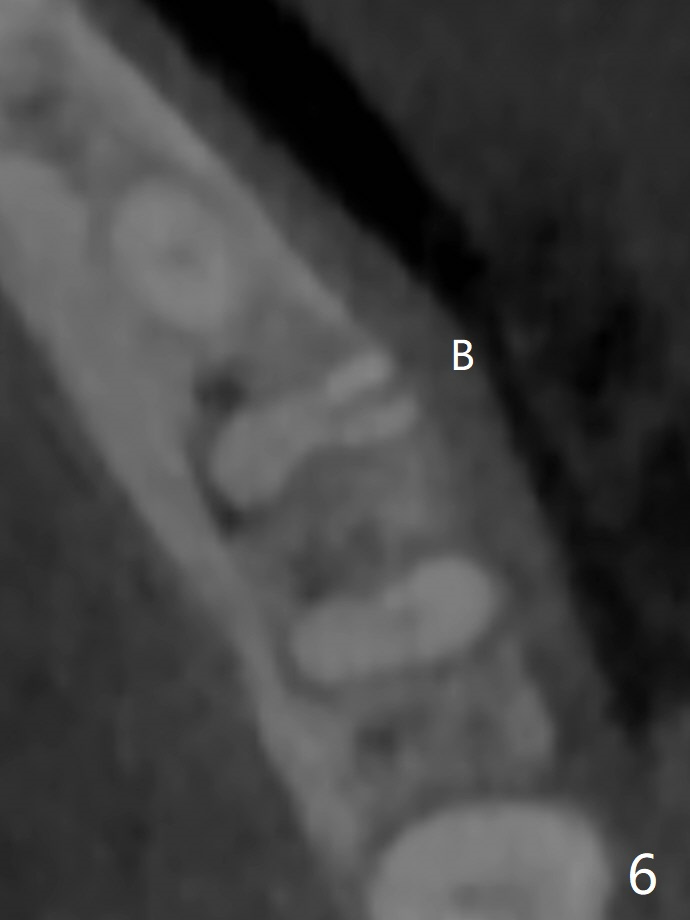

57岁女全口牙龈萎缩骨质吸收,其实卫生好,3号牙金属圈多年,治疗牙齿隐裂,骨质吸收和牙裂与咀嚼力大有关。最近抱怨19,30号牙敏感(图一),涂脱敏剂无效,拍摄根尖片(图二,三),显示30号牙远中根,19号牙近中根从牙槽嵴开始仿佛纵裂(图二,三),牙周探针患根周围触痛。磨牙牙根好像一段式植体,断裂总是发生于牙槽嵴顶,不过是横裂,所以一定要植入牙槽嵴之下,还要考虑今后牙槽嵴吸收。如何确诊牙根纵裂呢?例如19号牙CT显示颊侧近中根(图四,六:B)牙槽嵴处断裂(箭头)。利用一个叫Profile Program(Profilogram)测定近中根横断面平均密度,舌侧密度基本均匀(图七),而颊侧断裂处密度突然降低(图八)。当断裂还不是很明显时(隐裂),测定平均密度就显得重要,帮助诊断。